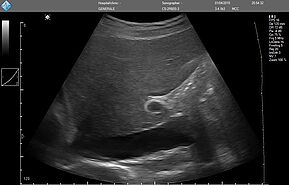

Исследование FAST (Сфокусированная сонографическая оценка при травме) позволяет выявить наличие жидкости в предполагаемых клинических условиях, визуализируя 10 структур или пространств в четырех областях:

- Перикардиальной

- Околопеченочной

- Околоселезеночной

- Тазовой

E-FAST (расширенный-FAST) дополнительно обследует переднюю и боковую плевральную полость (торакальная проекция) для оценки наличия пневмоторакса или плеврального выпота, предположительно гемоторакса у пациентов с травмой.